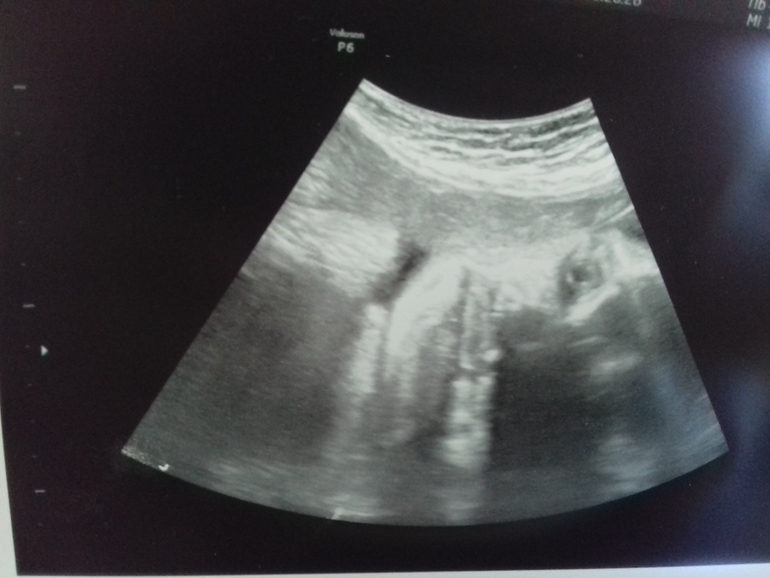

УЗИ, КТГ, доплерВ 33 недели нам наконец-то удалось запечатлить мордашку нашей пузожительницы) Скинула фото подруге, а она говорит - почему глаза открыты?(точнее на фото виден только один глаз)

Полезла в тырнет смотреть УЗИ на этом сроке, и правда, в основном все малышки с закрытыми глазами) А как было у вас?)

Она лежит, глаз один и он сверху, тут как бы пол-лица. То что открывают это понятно, удивило что на УЗИ это удалось запечатлить)